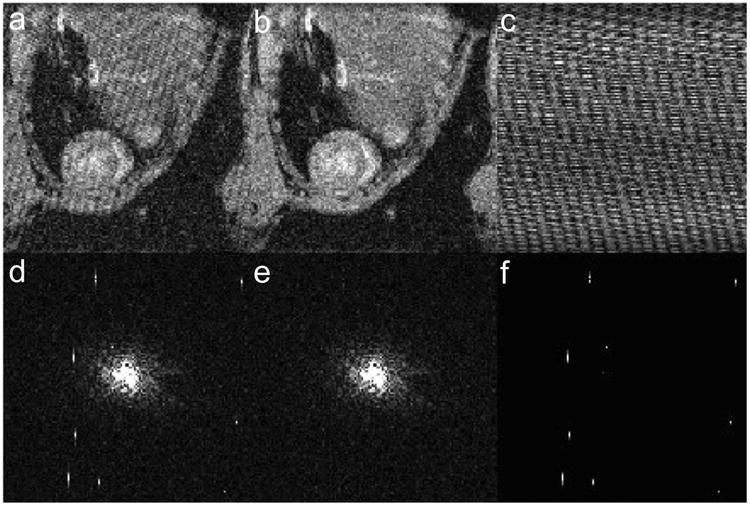

Figure 1.

Images (a-c) and k-space data (d-f) for a single frame of a T1 mapping data set. Corrupted data (a, d) is decomposed into low-rank (b, e) and sparse (c, f) components to isolate RF spikes (visible in f) and remove stripe artifact (visible in a). All the frames of the T1 recovery curve are shown in Video 1 (online supporting information).